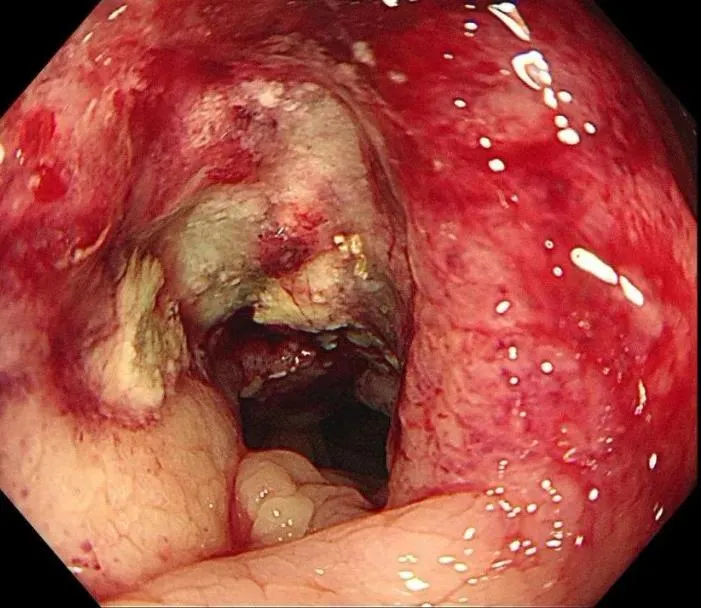

三天后,消化内镜中心孙舒仰医生操作的结肠镜顺利进行。当镜头探至升结肠近肝曲——正是之前查体摸到包块的位置时,一个不规则肿物赫然出现: 它环绕肠腔 2 /3,表面糜烂溃疡还附着污苔,质地脆弱一碰就出血,肠壁已变得僵硬,管腔也出现偏心性狭窄,万幸肠镜还能勉强通过。“高度怀疑结肠癌。” 孙舒仰医生当场判断。

别把“排便后腹痛缓解”当小事!年轻女孩的经历警示:肠癌信号可能很隐蔽插图1